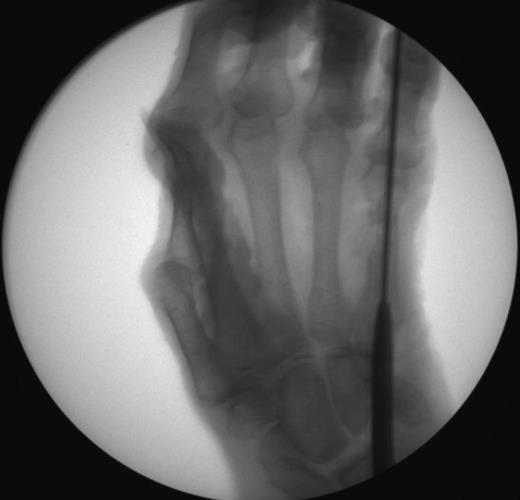

• step 4

• insert a 1.4mm k-wire through the drill guide hole that is 5mm greater than the chosen nail length for distal provisional fixation

• insert a 1.4mm k-wire through the most proximal drill guide hole for proximal provisional fixation

• step 5

• make a small incision to prepare for drilling and screw insertion, and bluntly spread the soft tissues with skin hooks

• carefully identify and protect the extensor tendons

• step 6

• advance the 2.0mm stop drill through the selected proximal slot, drilling through the near cortex until the mechanical stop reaches the drill guide

• measure screw length with the 1.4mm drill, stopping before the far cortex

• insert the selected 1.8mm locking compression screw unicortically

• step 7

• confirm final reduction and implant position using fluoroscopy

• step 8

• repeat the drilling, sizing, screw insertion, and fluoroscopic confirmation steps for the distal screw, taking note of the chosen hand nail length and the drill guide etched sizes

• step 9

• disengage the drill guide locking screw with the cruciform driver and remove the drill guide assembly